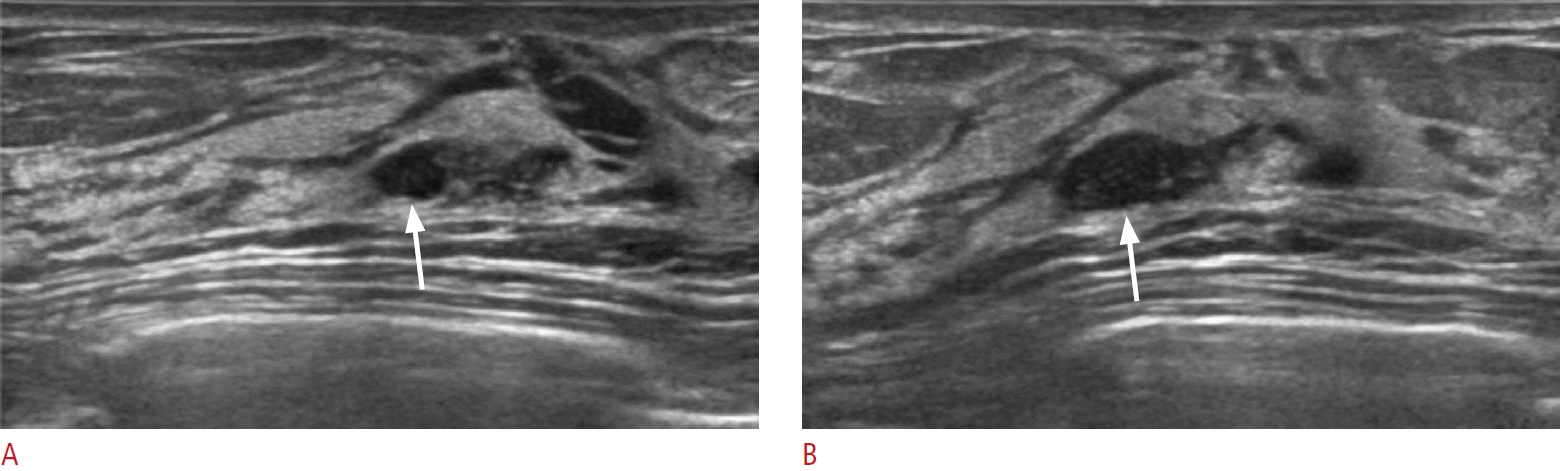

17. Ban K, Tsunoda H, Watanabe T, Kaoku S, Yamaguchi T, Ueno E, et al. Characteristics of ultrasonographic images of ductal carcinoma in situ with abnormalities of the ducts. J Med Ultrason (2001). 2020; 147:107–115.